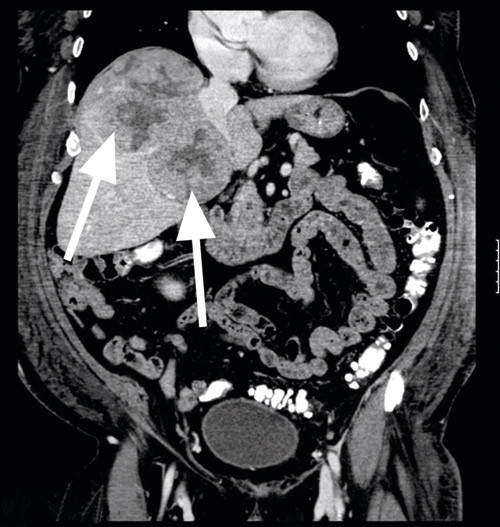

Pasienten ble så vurdert av øre-nese-hals-lege, som ikke fant tegn til malign sykdom i munnhule, hals eller svelg. Undersøkelse av perifert blod viste uttalt lymfopeni, men ellers normal mikroskopi og immunofenotyping. Undersøkelse av beinmarg viste kun uttalt lymfopeni, og ved immunofenotyping ble det ikke funnet patologiske forhold. CT-undersøkelse av abdomen viste imidlertid en stor tumor i høyre leverlapp (diameter 143 x 168 x 150 mm) og en liten tumor i venstre leverlapp (diameter 7 x 14 x 10 mm) (fig 2). CT-undersøkelse av thorax viste utstansede lesjoner i de tre første lumbalvirvlene forenlig med skjelettmetastaser. Baktil i høyre niende ribbein ble det påvist en destruerende tumoroppfylning som ekspanderte og infiltrerte åttende interkostalrom (fig 3). Alfaføtoprotein (AFP) var sterkt forhøyet (1 440 kU/l og steg senere til 1 600 kU/l)(normalt < 14).

Funnene av leversvulster sammen med metastaser til virvler og ribbein samt sterkt forhøyet alfa-1-føtoprotein var nærmest diagnostisk for hepatocellulært karsinom. Pasienten ble vurdert inoperabel både med hensyn til tumorreseksjon og levertransplantasjon.